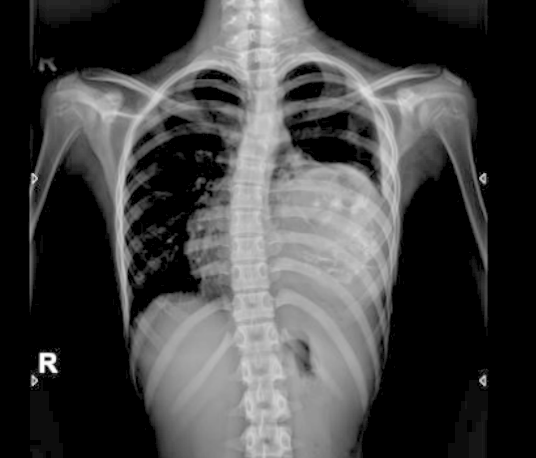

从胸片可以看到肿瘤占据了左侧大部分的胸腔,左肺已经被压缩到胸腔上部很小一个区域,气管受压向右侧偏移;心脏也受压向右侧胸腔移位;因为两侧胸腔压力的不对称,脊柱也有一定程度的侧弯。

胸片可见左侧胸腔巨大肿瘤压迫心肺